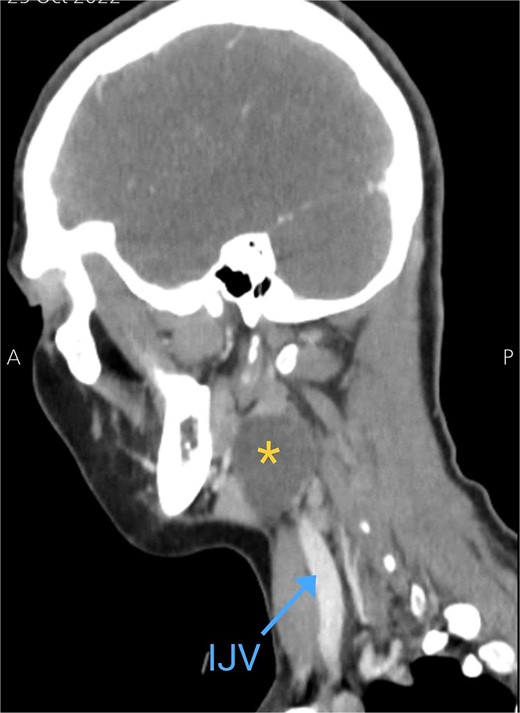

Soft tissue ultrasound revealed a well-demarcated, oval-shaped, homogeneously hypoechoic with internal debris mass and posterior acoustic enhancement, measuring about 3.8 × 4.7 cm. Axial (Fig. 2), sagittal (Fig. 3), and coronal (Fig. 4) neck computed tomography (CT) scans with intravenous (IV) contrast confirmed the presence of a cystic mass measuring 4.2 × 3.1 cm with centered fluid density and thin walls, lying over the common carotid artery (CCA), internal carotid artery (ICA), and external carotid artery (ECA), partially compressing the internal jugular vein (IJV) and ECA coinciding with second branchial cleft cyst.

Sagittal CT neck scan showing the branchial cleft cyst. Asterisk: branchial cleft cyst, blue arrow: IJV.